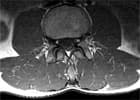

Das abgebildete Kernspin (oberes Bild) zeigt die Muskelverfettung bei einer Patientin, die 5 Jahre lang an therapieresistenten Schmerzen litt. Sie wurde übrigens durch ein gezieltes Krafttraining im MedX-Gerät beschwerdefrei.

Das unten abgebildete Kernspin zeigt gesunde Rückenstrecker. Die fettige Degeneration der Rückenstrecker bei der Patientin ist in der Tat ein krasser Fall. Etwa 60% des Muskelquerschnittes der Patientin ist verfettet. Hier ist nicht mehr viel Kraft da, welche die WS stabilisieren kann.

Die abgebildete Verfettung ist sicher ein Extremfall. Nicht jedes Kernspin sieht so aus. Aber Extremfälle schärfen das Verständnis für das Prinzip:

Schwache Muskeln – fehlende Stabilität – Schmerzen